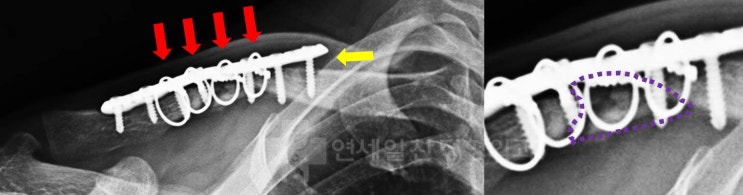

회전근개 재파열, 회전근개 재수술, 상부관절낭재건술

이번 케이스는 회전근개 일차 봉합술이 잘못되어 재파열이 일어난 경우이다. 환자는 10개월전 수술적 치료...